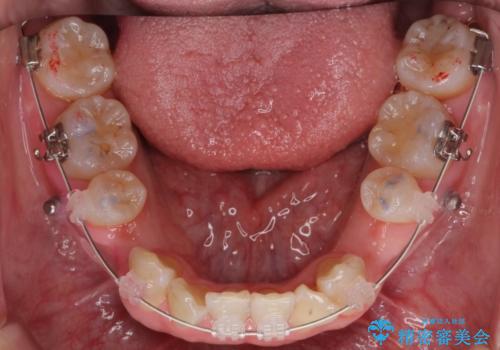

- ハーフリンガル

矯正治療で右下を抜歯し、スペースを天然の歯でつめる矯正治療を行いました。

上顎前歯も唇側傾斜しておらず、もともと叢生が多くない状態で上下左右を抜歯した上、リンガルで治療を行なったため、多少治療期間がかかりました。